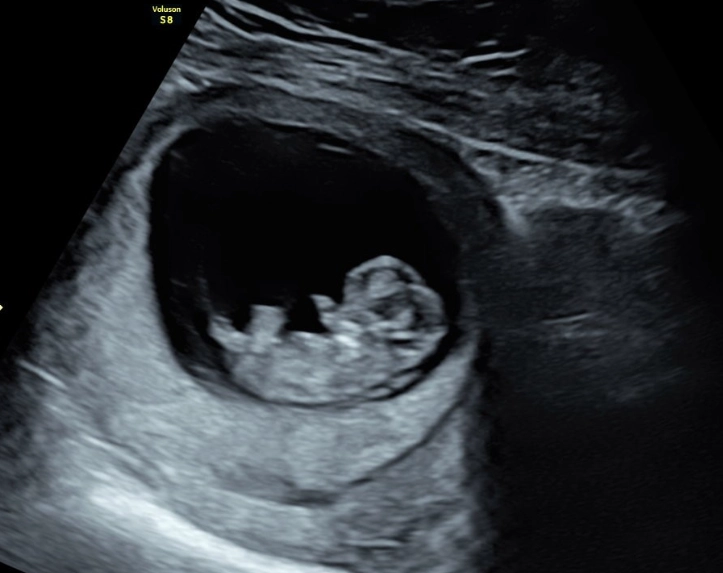

After all this talk of signs and symptoms, remember the bigger picture. A normal pregnancy isn't defined by a perfect checklist of symptoms. It's defined by the healthy progression confirmed through your prenatal appointments: steady weight gain, a growing fundal height (the measurement of your belly), a strong fetal heartbeat, and normal ultrasound findings.